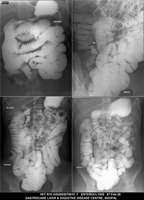

Section: ENTEROCLYSIS Total: 205 images

BaM Enteroclysis Loopogram BaE Fistulogram Urethrogram HSG